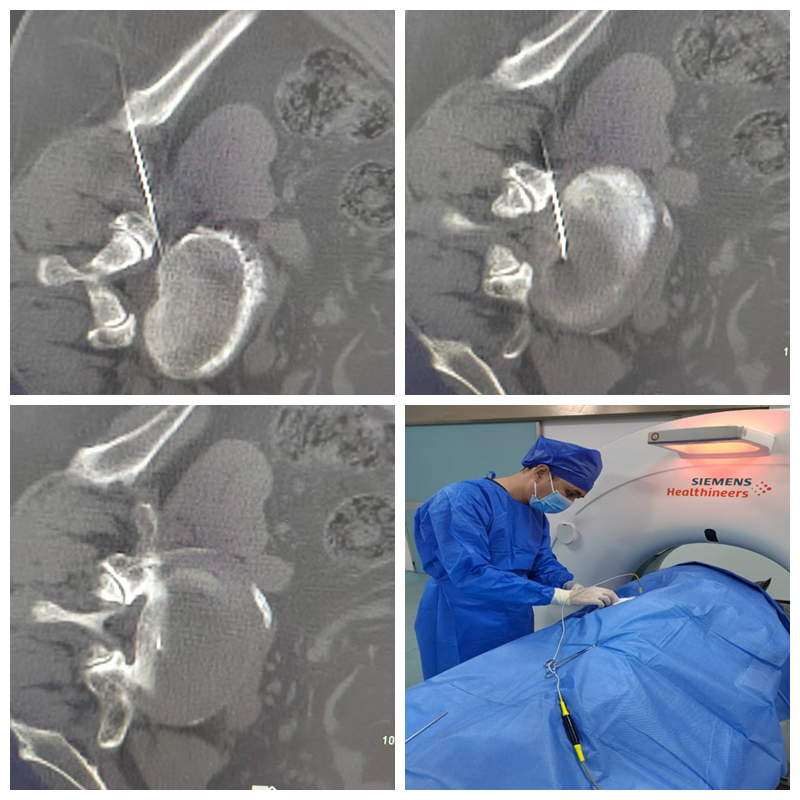

能完成该标准要求的绝大多数手术,包括选择性神经根阻滞技术、交感神经丛(干)介入医治技术、颅神经介入医治技术、神经射频调制技术、腰椎间盘介入医治技术、颈椎间盘介入医治技术、外周神经射频技术、脊髓电刺激、椎体成形术、硬膜外造影术、椎间盘造影术等。

神经射频调制技术